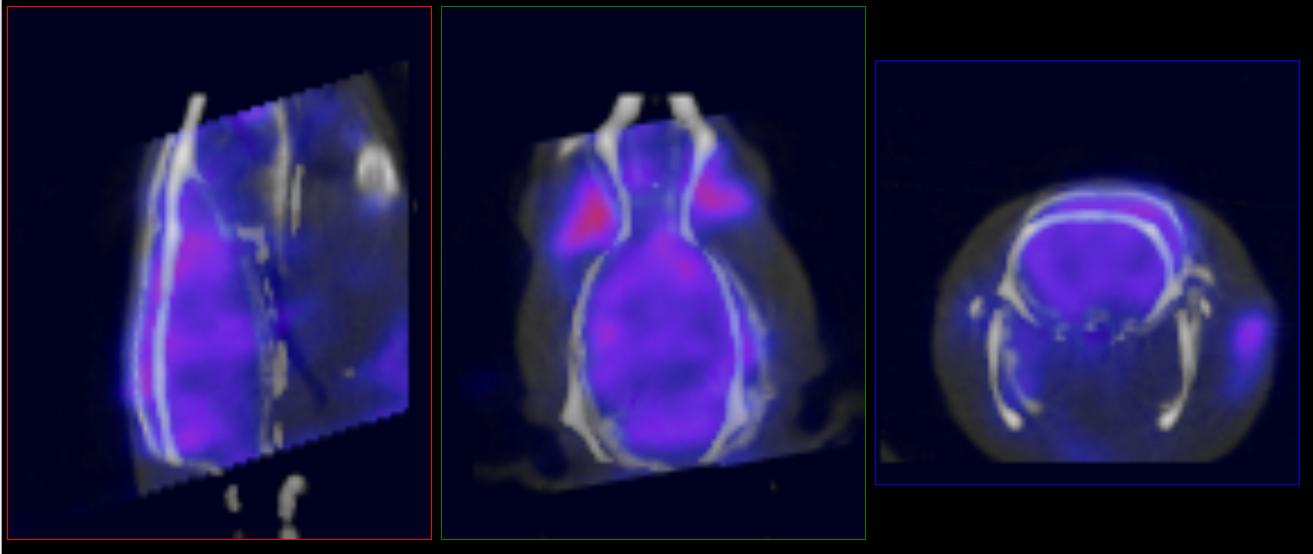

| data.csv | Uptake and concentration data for each brain region for each input frame |

| data-montage.png | QC image of ROI fitted to data |